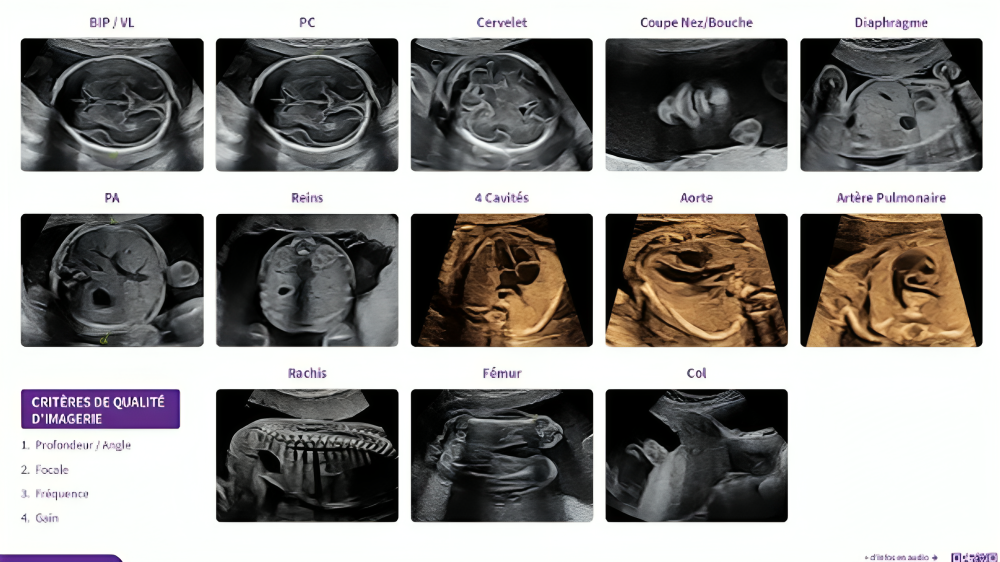

L’échographie dite morphologique du 2e trimestre :

Au deuxième trimestre, l’échographie dite morphologique étudie de façon méthodique l’anatomie du futur bébé. L’examen dure un peu plus longtemps que le premier, il permet d’observer les membres ainsi que les différents organes du fœtus (cerveau, cœur, reins, estomac…), de s’assurer de leur bonne évolution et de dépister d’éventuelles malformations. C’est aussi le moment pour les parents qui le souhaitent de découvrir le sexe de leur enfant !